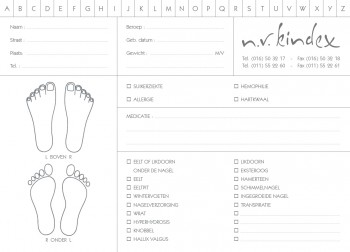

- manicure

- pedicurie (2)